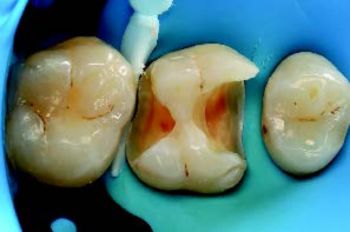

Etter isolering med kofferdam og pre-kiling ble den gamle restaureringen fjernet med diamantbor under vannkjøling. Kaviteten ble renset og behandlet med 27 μm aluminiumoksid via luftabrasjon. Siden kuspene var >2 mm, var kuspedekke unødvendig (Fig. 2).

Figur 2: Ferdig kavitet etter partikkelbasert luftabrasjon.